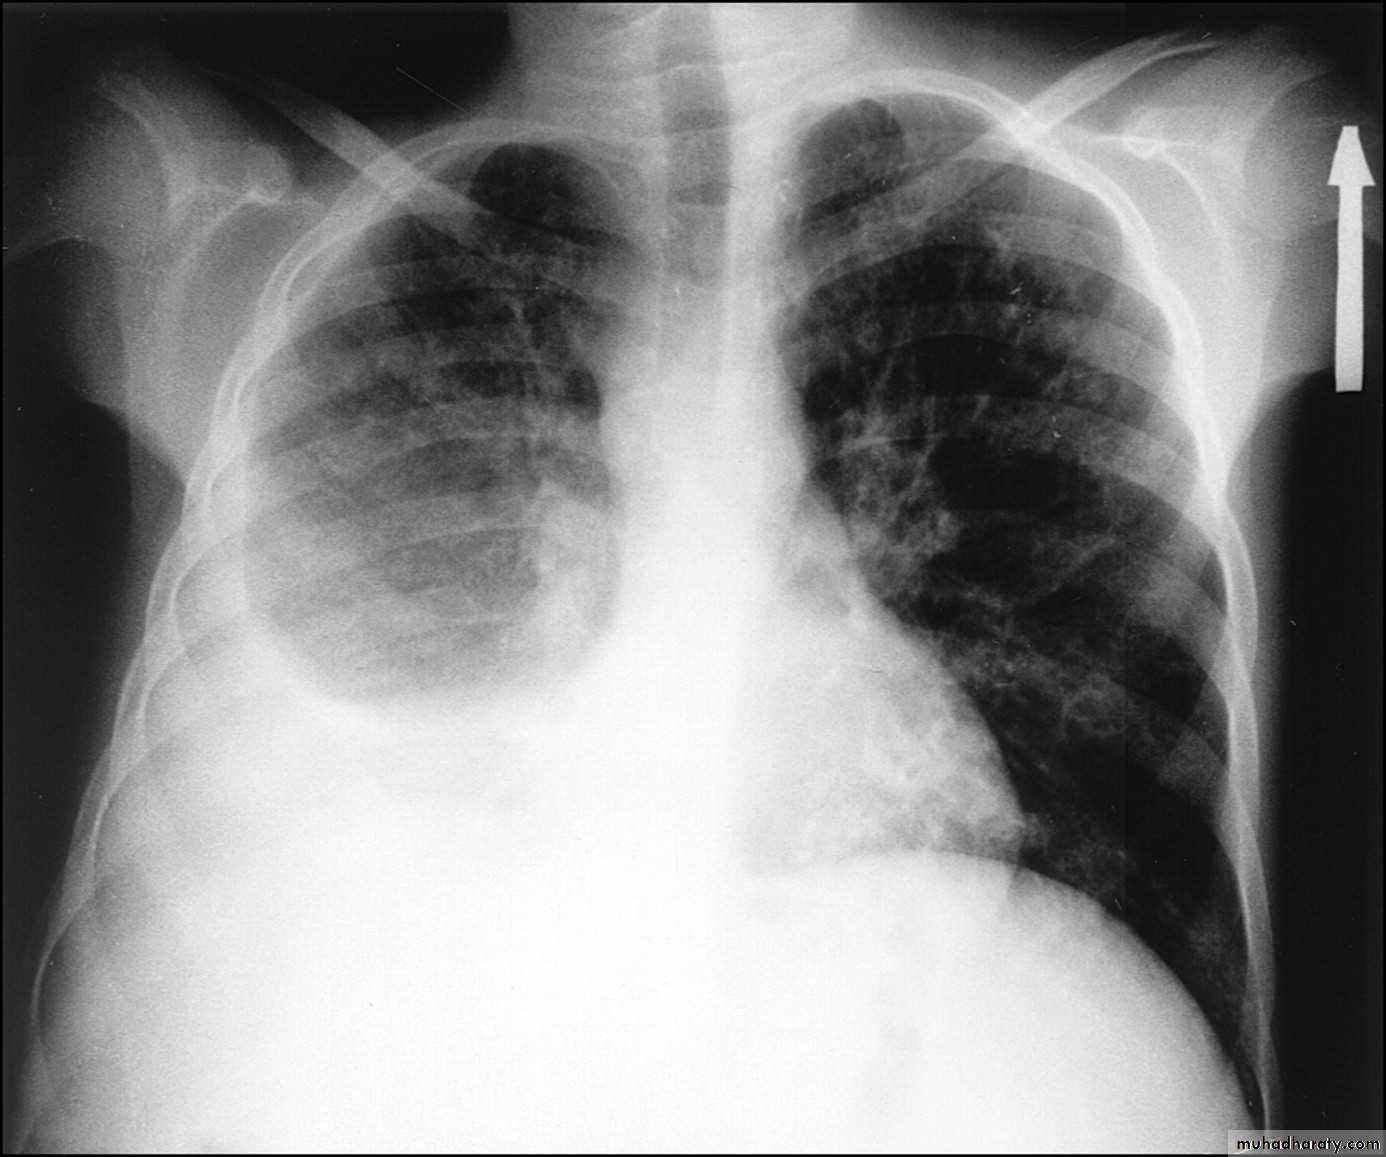

Right upper lobe consolidation

RUL consolidation will be seen as an increased opacity within the right upper lobe. Opacity may be sharply bordered by the horizontal fissureSome loss of outline of the upper right heart border may be apparent

Radiological sign in chest radiograph

Dense opacity seen above the horizontal fissure.

Air-bronchogram line

The lower border of the consolidation is sharply delinated by the horizontal fissure suggesting it lies in the anterior segment of the RUL